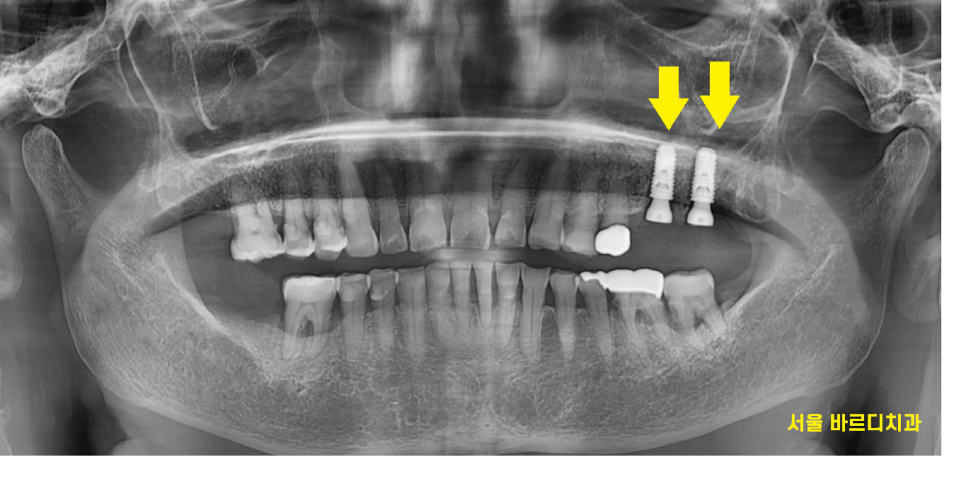

23.06.27

엑스레이상 치석도 보이고..

잇몸뼈도 많이 내려가

풍치가 진행된 상태였는데요.

잇몸치료는 필수로 진행하시고...

뼈가 많이 녹은 왼쪽 위에는

뽑아야할꺼같다고 조심스레 말씀드렸습니다.

겉으로는 멀쩡해 보이는데

속은 다.. 녹아서

흔들리고 있었거든요.